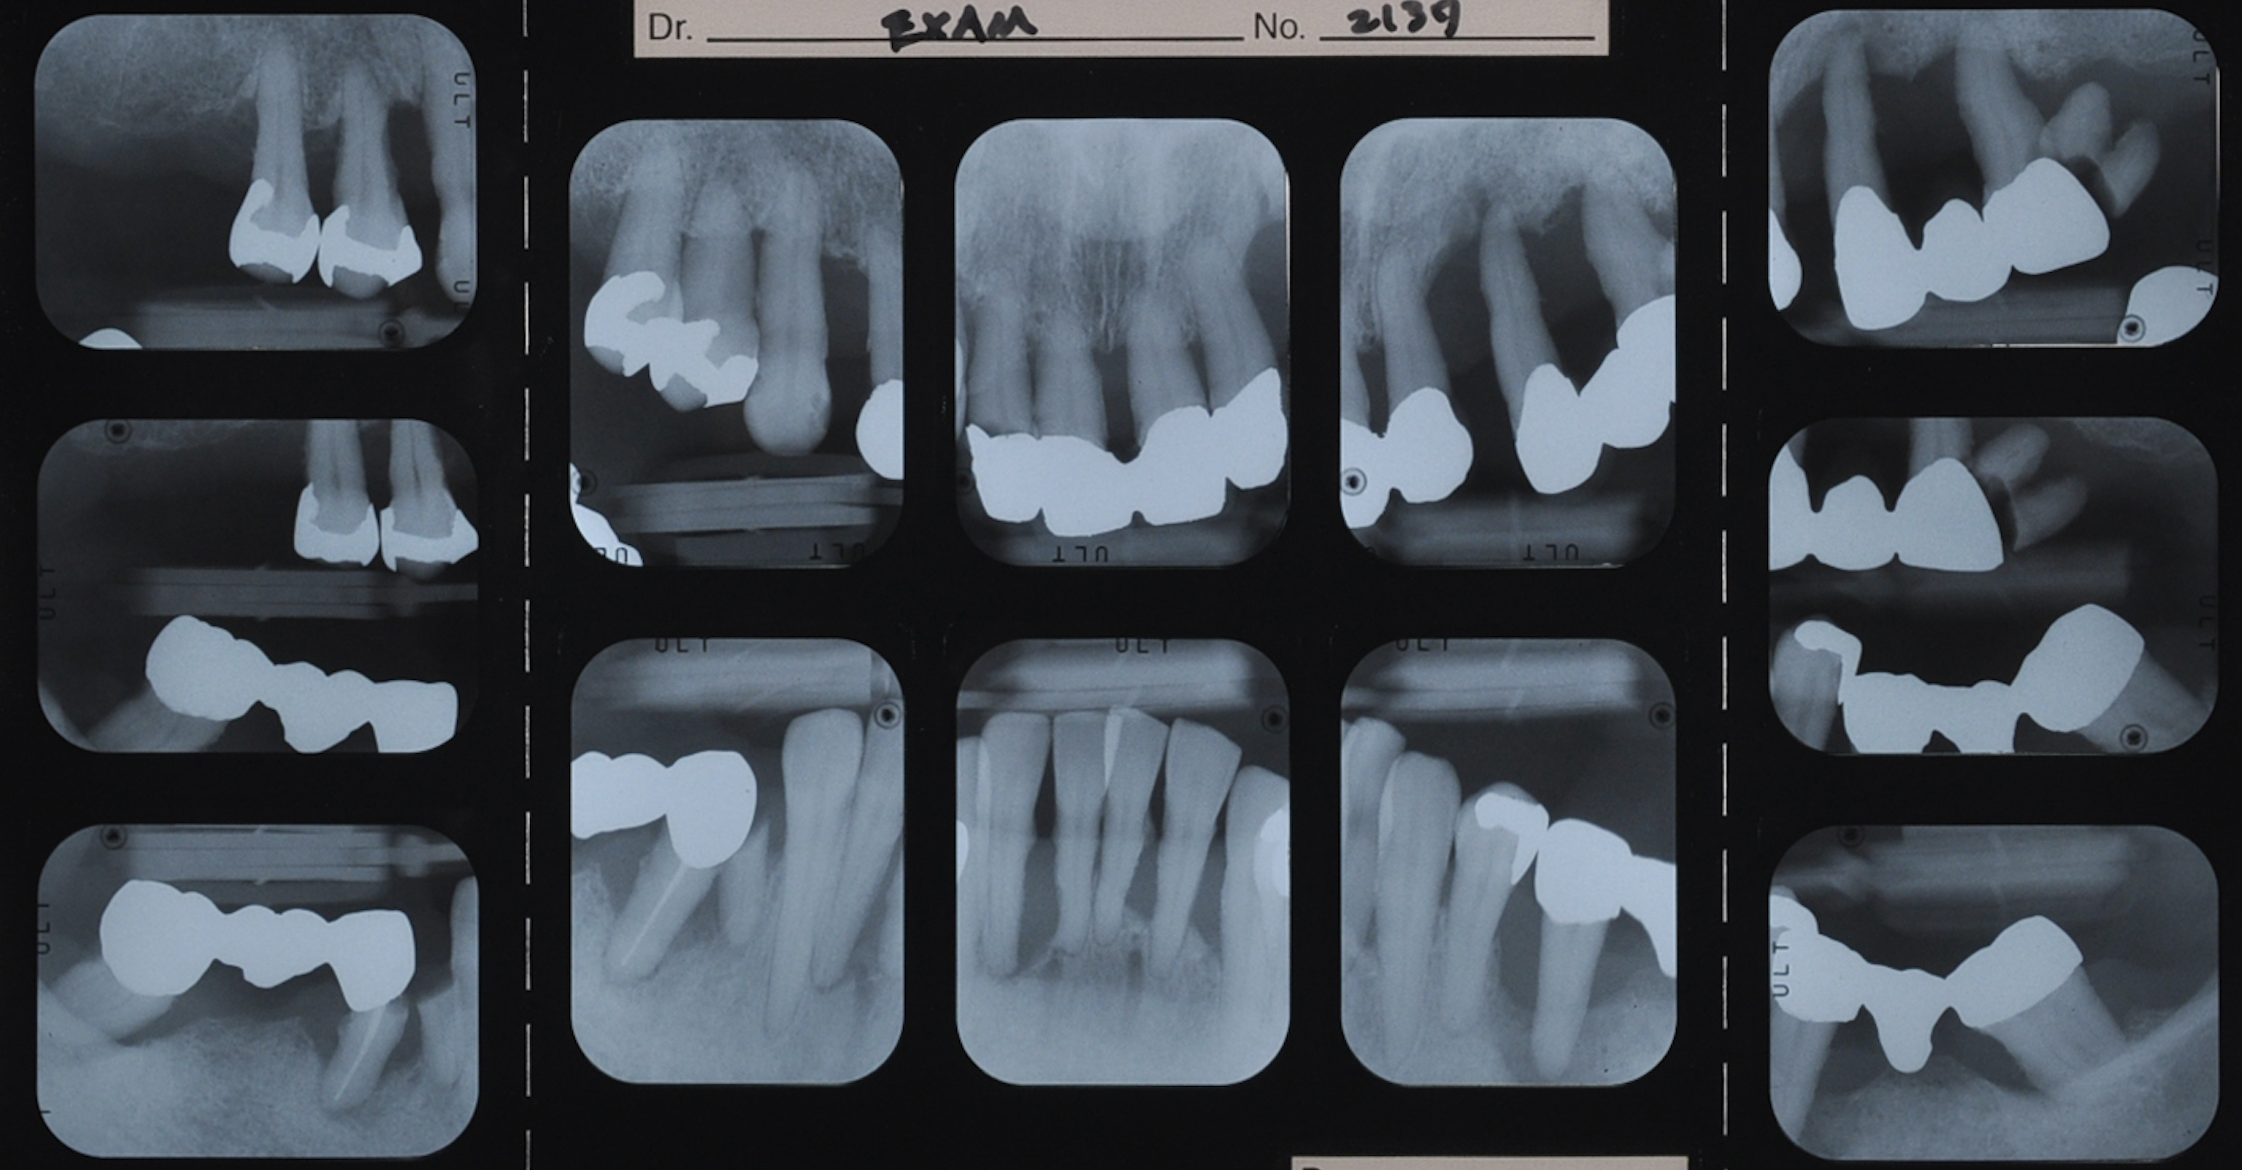

50代女性 部分義歯で対応した重度歯周病症例

ステージIVグレードB 審美障害

治療内容

歯周基本治療

歯周外科

抜歯

抜歯部位

FDI表記 23 25 26 35 37 42 44 45 47

治療期間

1年

通院回数

30

費用

170万円